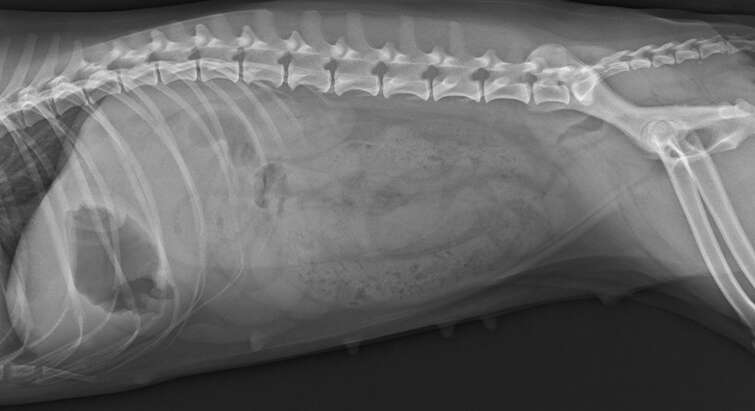

For at kunne uddanne og videreuddanne fremtidens dyrlæger, har vi brug for aflivede hunde, som de studerende kan øve undersøgelsesprocedurer og kirurgiske indgreb på.

Hvis du vil støtte dyrlægeuddannelsen, vil vi som tak tilbyde gratis aflivning af din hund døgnet rundt, når det er tid til at sige farvel.

Vær opmærksom på, at når du donerer din hund til dette formål, vil du ikke efterfølgende modtage et obduktionssvar.